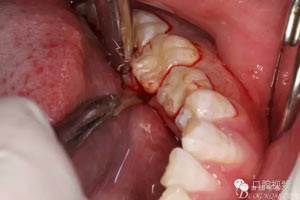

圖5.行齦溝內(nèi)水平切口,不建議做垂直附加切口,因為口底組織淺,容易水腫。風(fēng)險大。